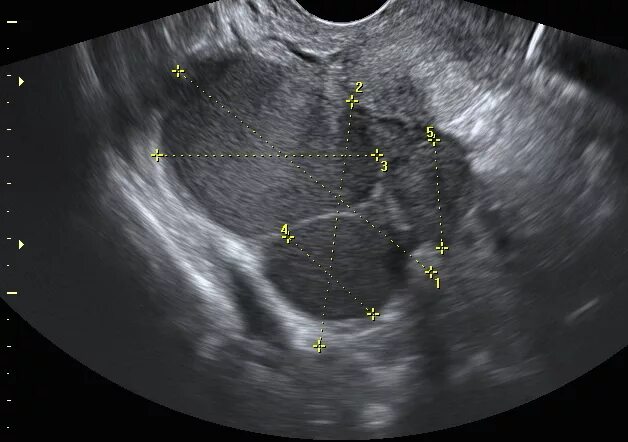

Эхо признаки кисты